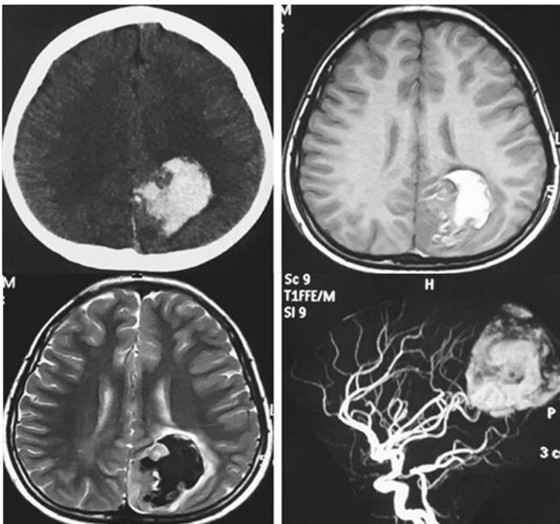

患者在2013年8月情绪激动大哭大闹后出现呕吐,低热,急诊就医以“急性胃肠炎处理”,具体治疗方案不详。次日患者出现脑膜刺激征,临床怀疑“脑膜炎”予以治疗。后行头颅CT时发现颅内出血,予以保守治疗;而后行MRI、MRA考虑AVM致出血可能(图1),规律随访。2015年3月MRI随访时考虑左侧顶部镰旁脑膜瘤可能(图2),考虑肿瘤切除而入院。患者在随访过程无特殊不适主诉,无明显阳性体征。

图1 2013-8-16首次CT、MRI及MRA影像

CT示左顶叶高密度为主混杂密度影,形态不规则,周围可见低密度区,后纵裂池密度增高;MRI符合亚急性早期脑内血肿改变;MRA提示左顶叶血肿区域与左侧大脑中动脉及大脑后动脉分支供血区域吻合,未见明显异常血管团